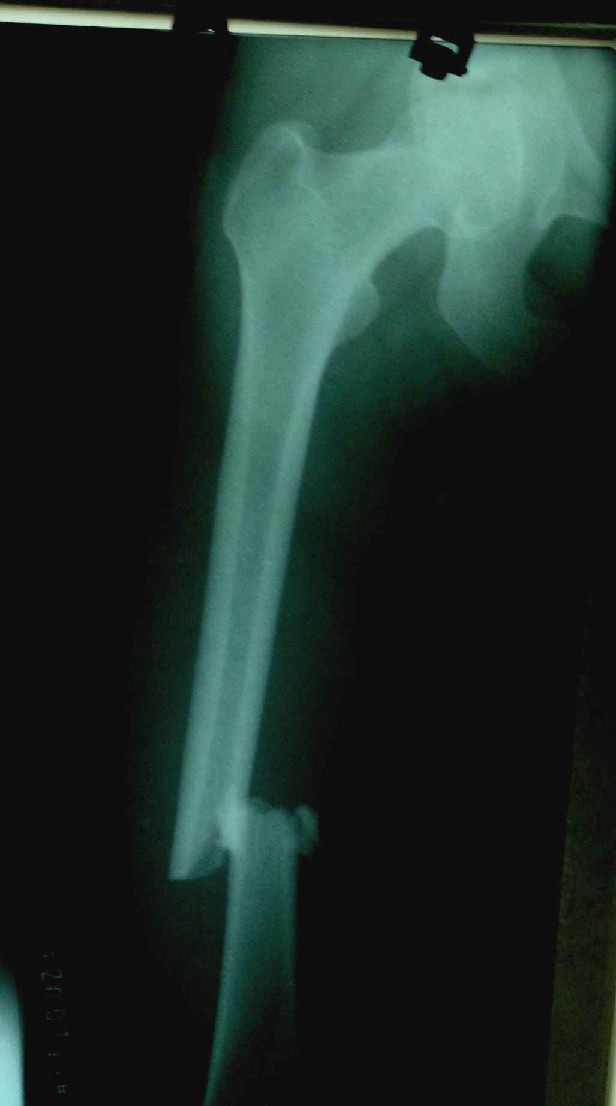

患者,女,因外伤就诊。摄骨盆及右股骨。当时报告骨盆未见明显异常,右股骨中段粉碎性骨折。五天后行股骨中段骨折内固定手术,术中摄床边片示股骨颈骨折。现把术前和术中图像上传。请大家高诊,分析股骨颈骨折是术前漏诊还是其他原因。术前骨盆片右股骨颈显示欠佳是由于股骨中段骨折无法将股骨颈完全显示。

术前片示右股骨颈未见明显骨折征象。如果事先有骨折,由于投照位置原因,骨折线也是完全有可能被挡住重叠而看不见的(并且本例骨折对位良好,更有可能看不到)。所以要凭此判断述前是否有骨折不容易

从上传的照片来看,术前无法诊断骨折。可能是投照角度的问题。

术前由于位置原因使股骨颈未全部显示,骨折线与股骨头重叠,骨折也可以使股骨颈缩短

术前所照的片子体位好象有点不标准,右侧股骨颈显示不是很好,没有完全展开,所以不好说术前就一定没有骨折的情况.